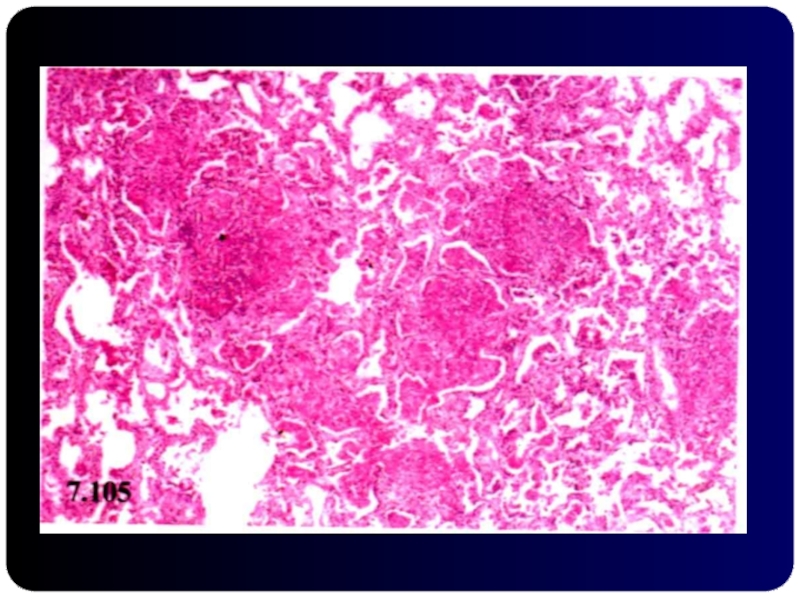

Слайд 72ДИССЕМИНИРОВАННЫЙ ТБ

Слайд 732.3. Диссеминированный ТБ легких

Кортико-плевральная локализация

Симметричность поражений

Продуктивная тканевая реакция

Очковый

характер каверн

Хроническое течение

Развитие сетчатого и очагового пневмосклероза

Развитие

эмфиземы легких

Развитие легочного сердца

2.3. Диссеминированный ТБ легкихКортико-плевральная локализация Симметричность поражений Продуктивная тканевая реакция Очковый характер каверн Хроническое течение Развитие сетчатого

Слайд 74Диссеминированный ТБ легких

Диссеминированный ТБ легких